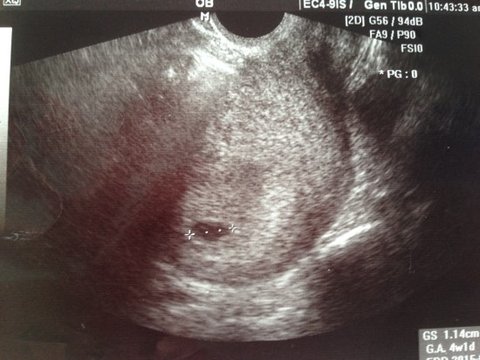

염증치료 결과확인을 위해 병원에서 초음파 검사를 받음.

초음파 검사를 시작하자마자 아기집 발견짱

다소 갑작스러운 임신에 나도, 폭매남도, 양가 부모님도 놀라셨음.

거북이 태몽을 반영하여 꼬부기라고 태명을 지음.

한동안 세쌍둥이는 아닐까 걱정아닌 걱정을 했으나 쌍둥이는 아니었음ㅋㅋ

거북이 태몽 덕분인지 지금까지 건강히 자라고 있는 꼬부기!!